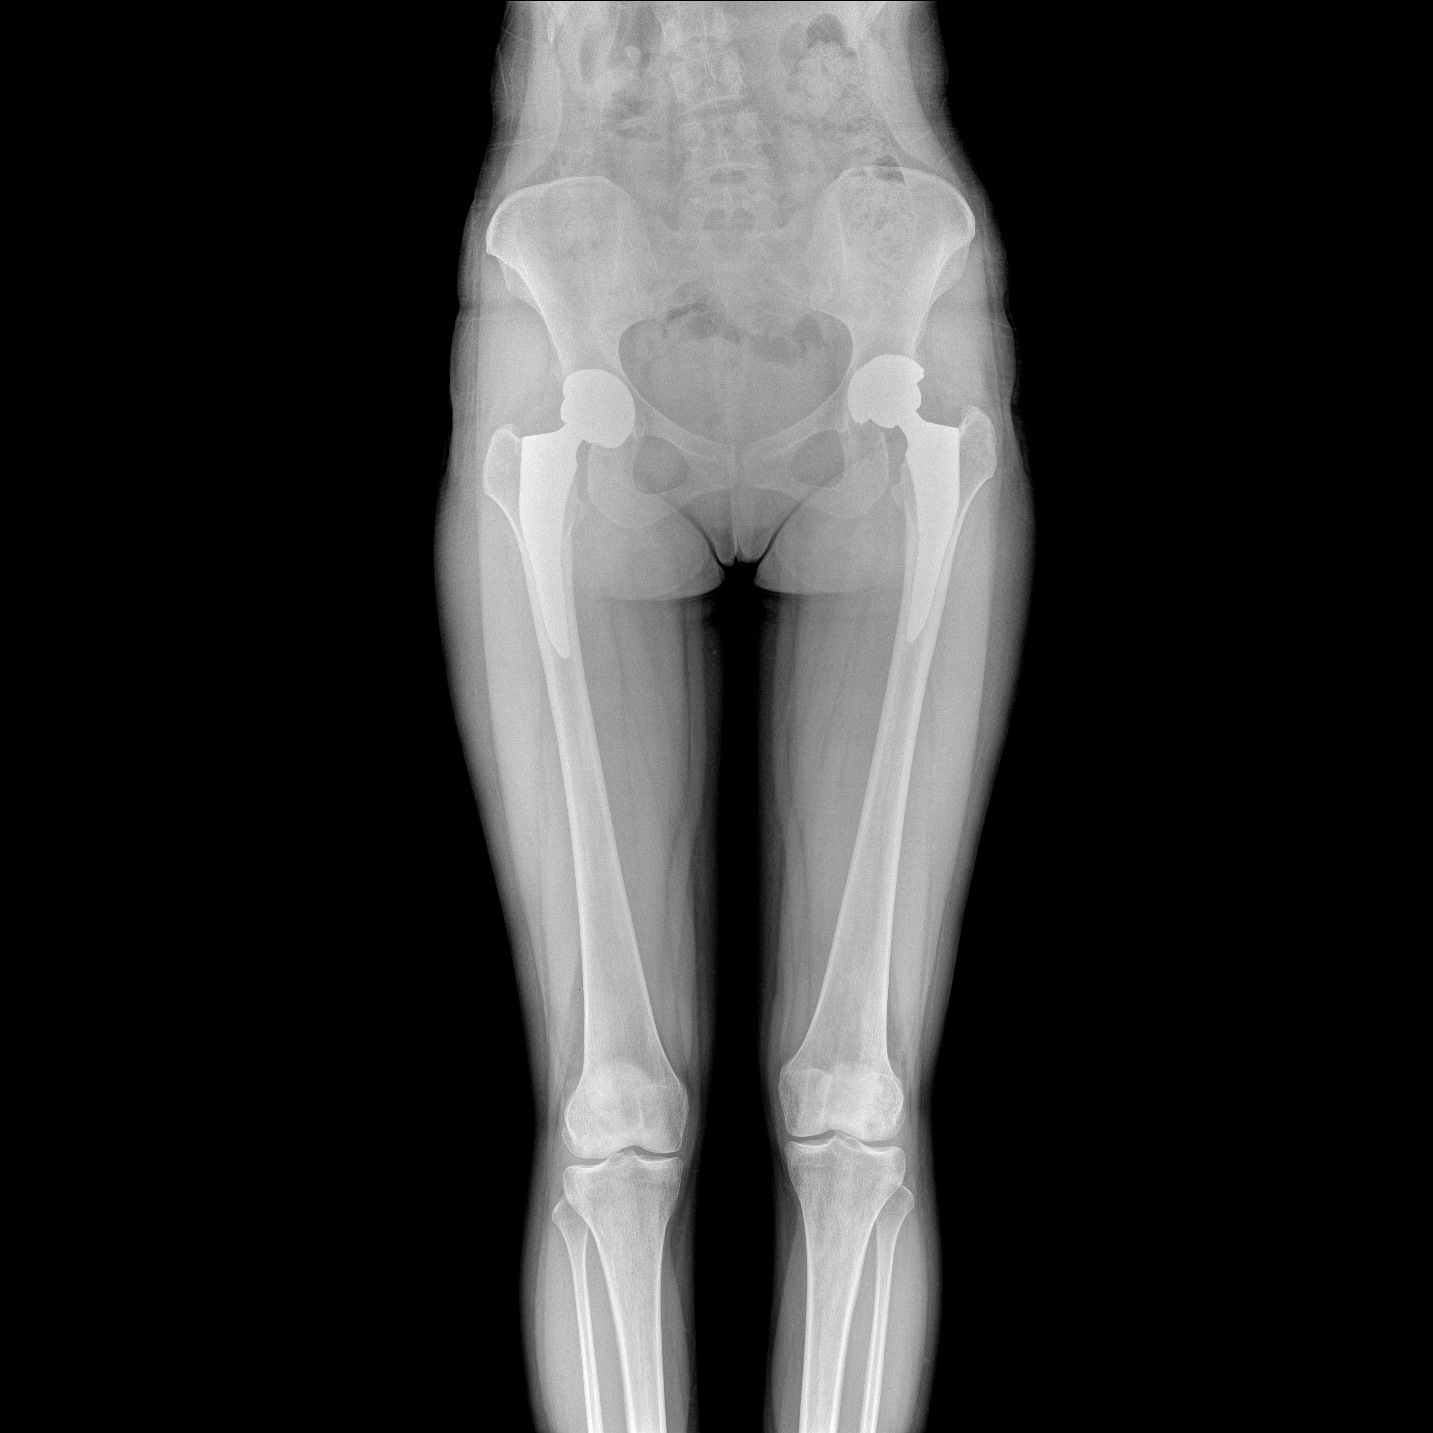

17"*34"有效視野,一次成像不拼接。相較于多張攝影再軟件拼接的DR設(shè)備,PLX8600解決了拼接圖像存在密度不均勻,拼接處圖像配準(zhǔn)和放大效應(yīng)等問(wèn)題,給臨床帶來(lái)了大視野影像解決方案,可一次性覆蓋全脊柱或雙下肢影像。

支持全脊柱攝影、雙下肢攝影、脊髓造影、復(fù)雜創(chuàng)傷、人工關(guān)節(jié)置換、關(guān)節(jié)損傷的修復(fù)重建等大視野臨床應(yīng)用